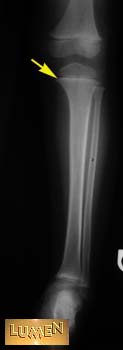

Question: Identify.

Answer

Medial condyle of tibia.